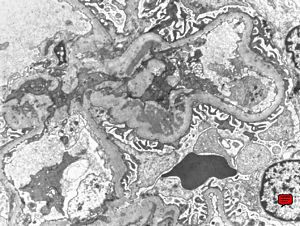

M,37y. | type I membranoproliferative glomerulonephritis (mesangiocapillary)